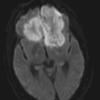

Mucormycosis - Zygomycosis